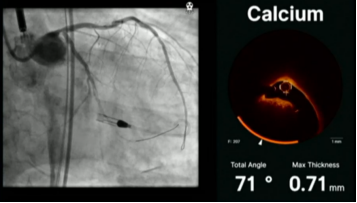

来自英国国王学院医院的Jonathan Hill教授展示了一例Shockwave IVL有效治疗偏心性钙化及钙化结节的病例。患者为77岁男性,胸痛主诉入院,OCT检查显示患者左主干远端明显狭窄,且在回旋支开口处有一个钙化结节(如图1、2)

除了分享案例,Jonathan Hill教授也结合既往使用IVL的经验谈到:OCT能帮助我们更精准的评估严重钙化的厚度、角度和长度等关键信息,可以根据OCT钙化积分的评估结果,根据病变需要,进行Shockwave IVL多个周期的脉冲释放,特别对于比较深层比较厚的钙化病变,IVL有其独特的临床效果和应用优势。